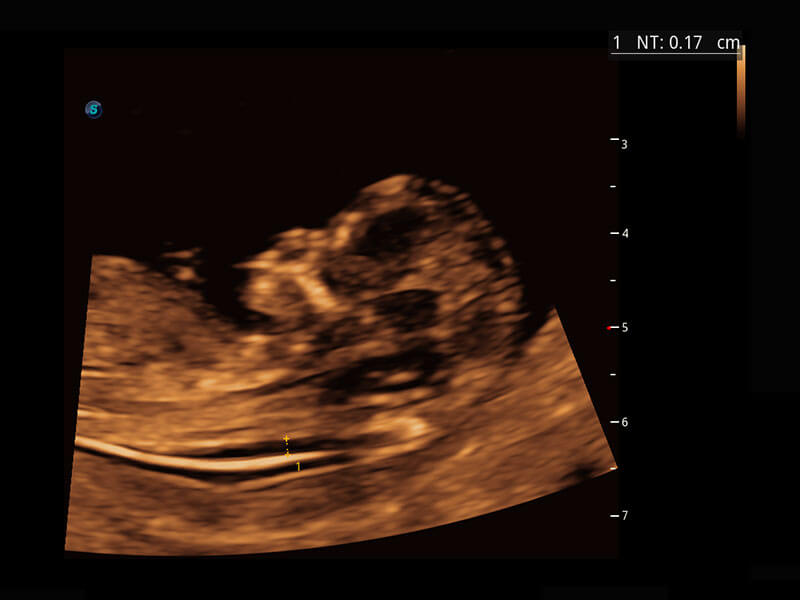

早孕筛查

根据国际妇产科超声协会ISUOG统计,早孕超声筛查结合胎儿游离染色体筛查(NIPT),能够检出大部分胎儿染色体异常疾病,P60在胎儿早孕期超声筛查中为您带来优异的图像质量。

• 早孕-胎心

• 高分辨率容积成像-早孕胎儿

• 胎儿体循环

• 光影成像-孕囊